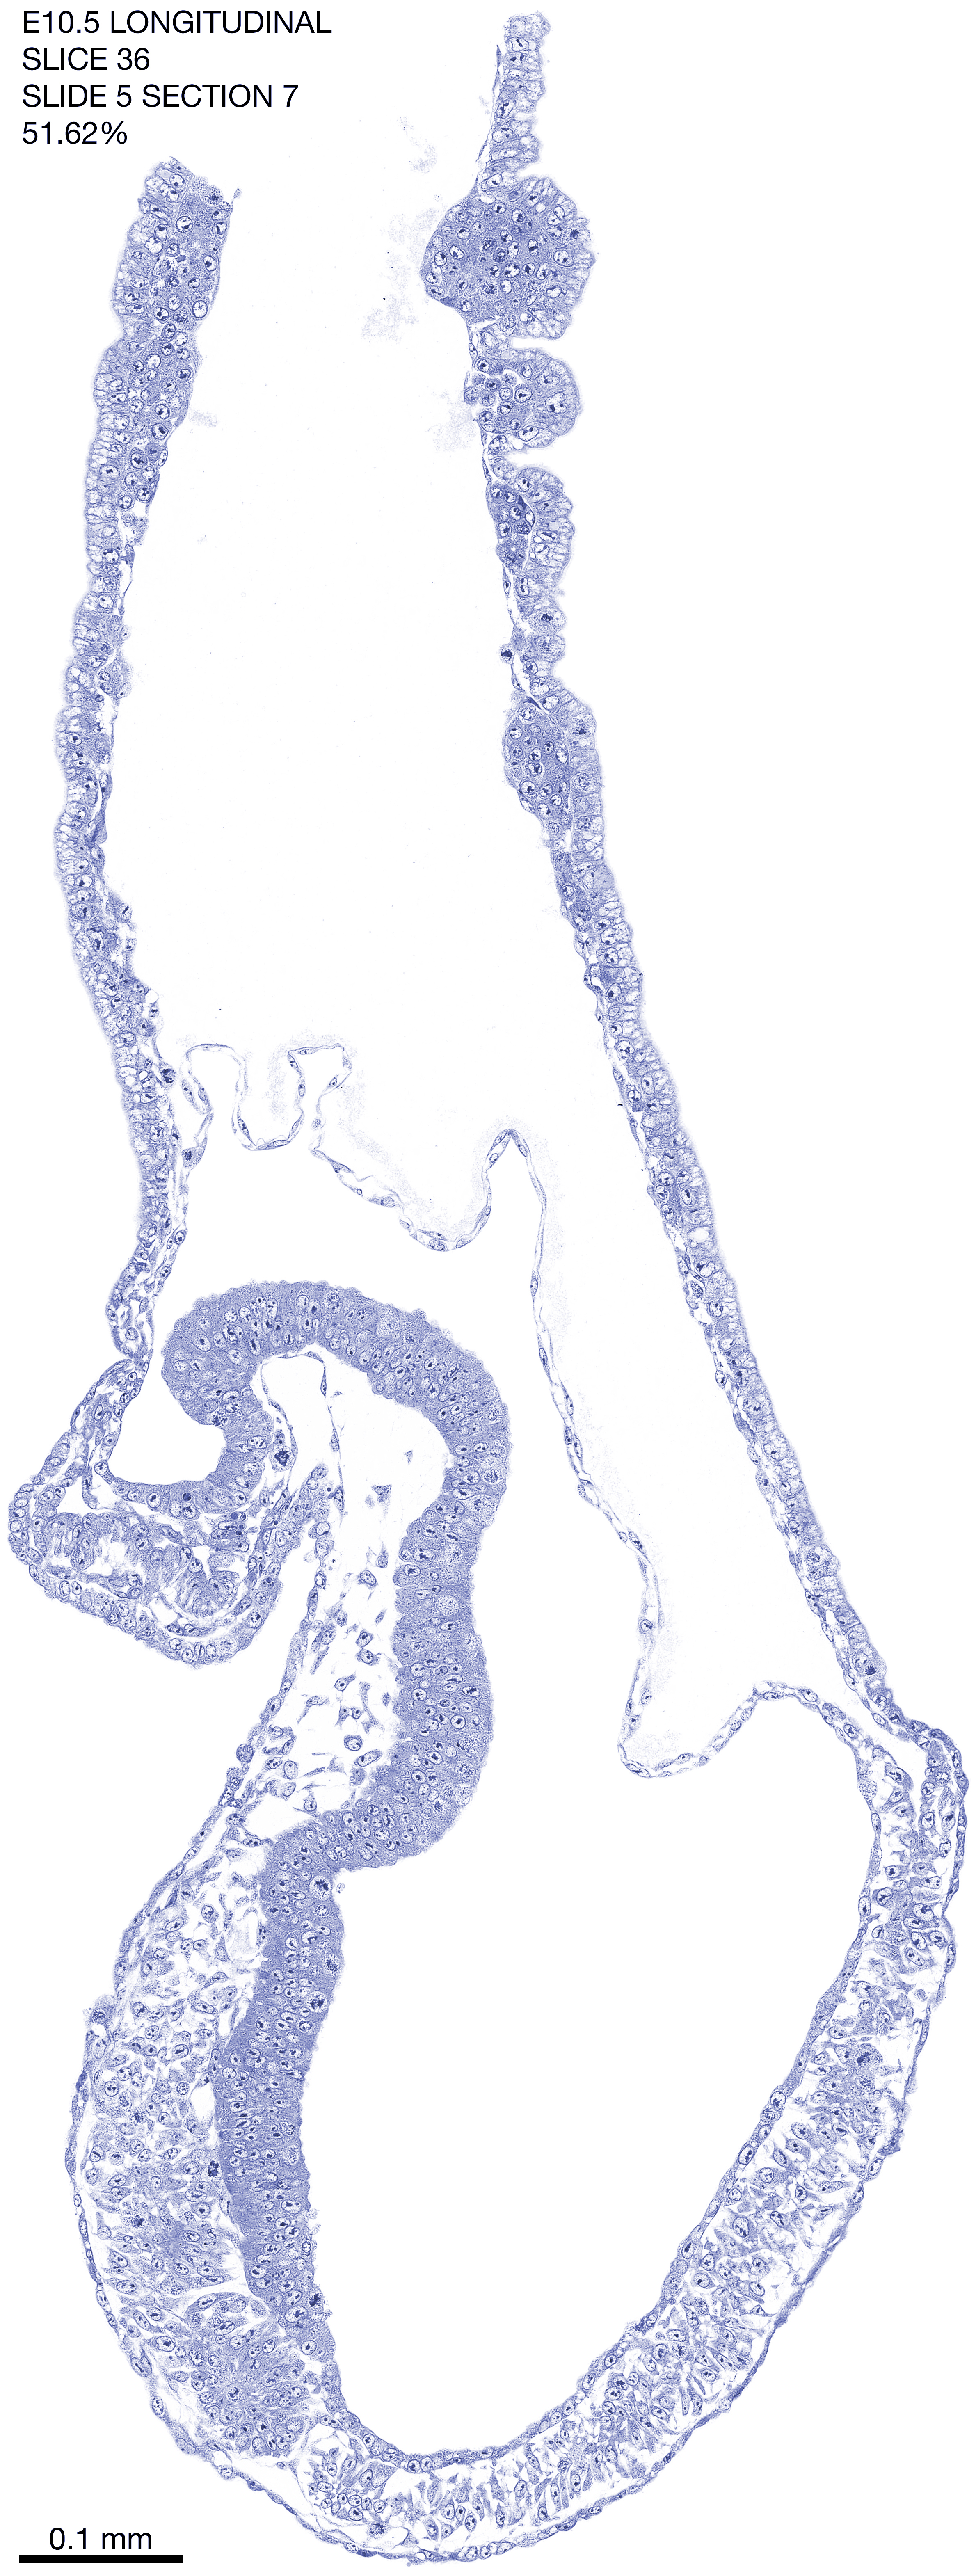

E10.5 Longitudianal Archive This page contains jpg files of ALL SLICES (each 3µm thick) that were scanned of the E10.5 longitudinally cut specimen. Download: Large | High Res Download: Large | High Res Download: Large | High Res Download: Large | High Res Download: Large | High Res Download: Large | High Res Download: Large | High Res Download: Large | High Res Download: Large | High Res Download: Large | High Res Download: Large | High Res Download: Large | High Res Download: Large | High Res Download: Large | High Res Download: Large | High Res Download: Large | High Res Download: Large | High Res Download: Large | High Res Download: Large | High Res Download: Large | High Res Download: Large | High Res Download: Large | High Res Download: Large | High Res Download: Large | High Res Download: Large | High Res Download: Large | High Res Download: Large | High Res Download: Large | High Res Download: Large | High Res Download: Large | High Res Download: Large | High Res Download: Large | High Res Download: Large | High Res Download: Large | High Res Download: Large | High Res Download: Large | High Res Download: Large | High Res Download: Large | High Res Download: Large | High Res Download: Large | High Res Download: Large | High Res Download: Large | High Res Download: Large | High Res Download: Large | High Res Download: Large | High Res Download: Large | High Res Download: Large | High Res Download: Large | High Res Download: Large | High Res Download: Large | High Res Download: Large | High Res Download: Large | High Res Download: Large | High Res Download: Large | High Res Download: Large | High Res Download: Large | High Res Download: Large | High Res Download: Large | High Res